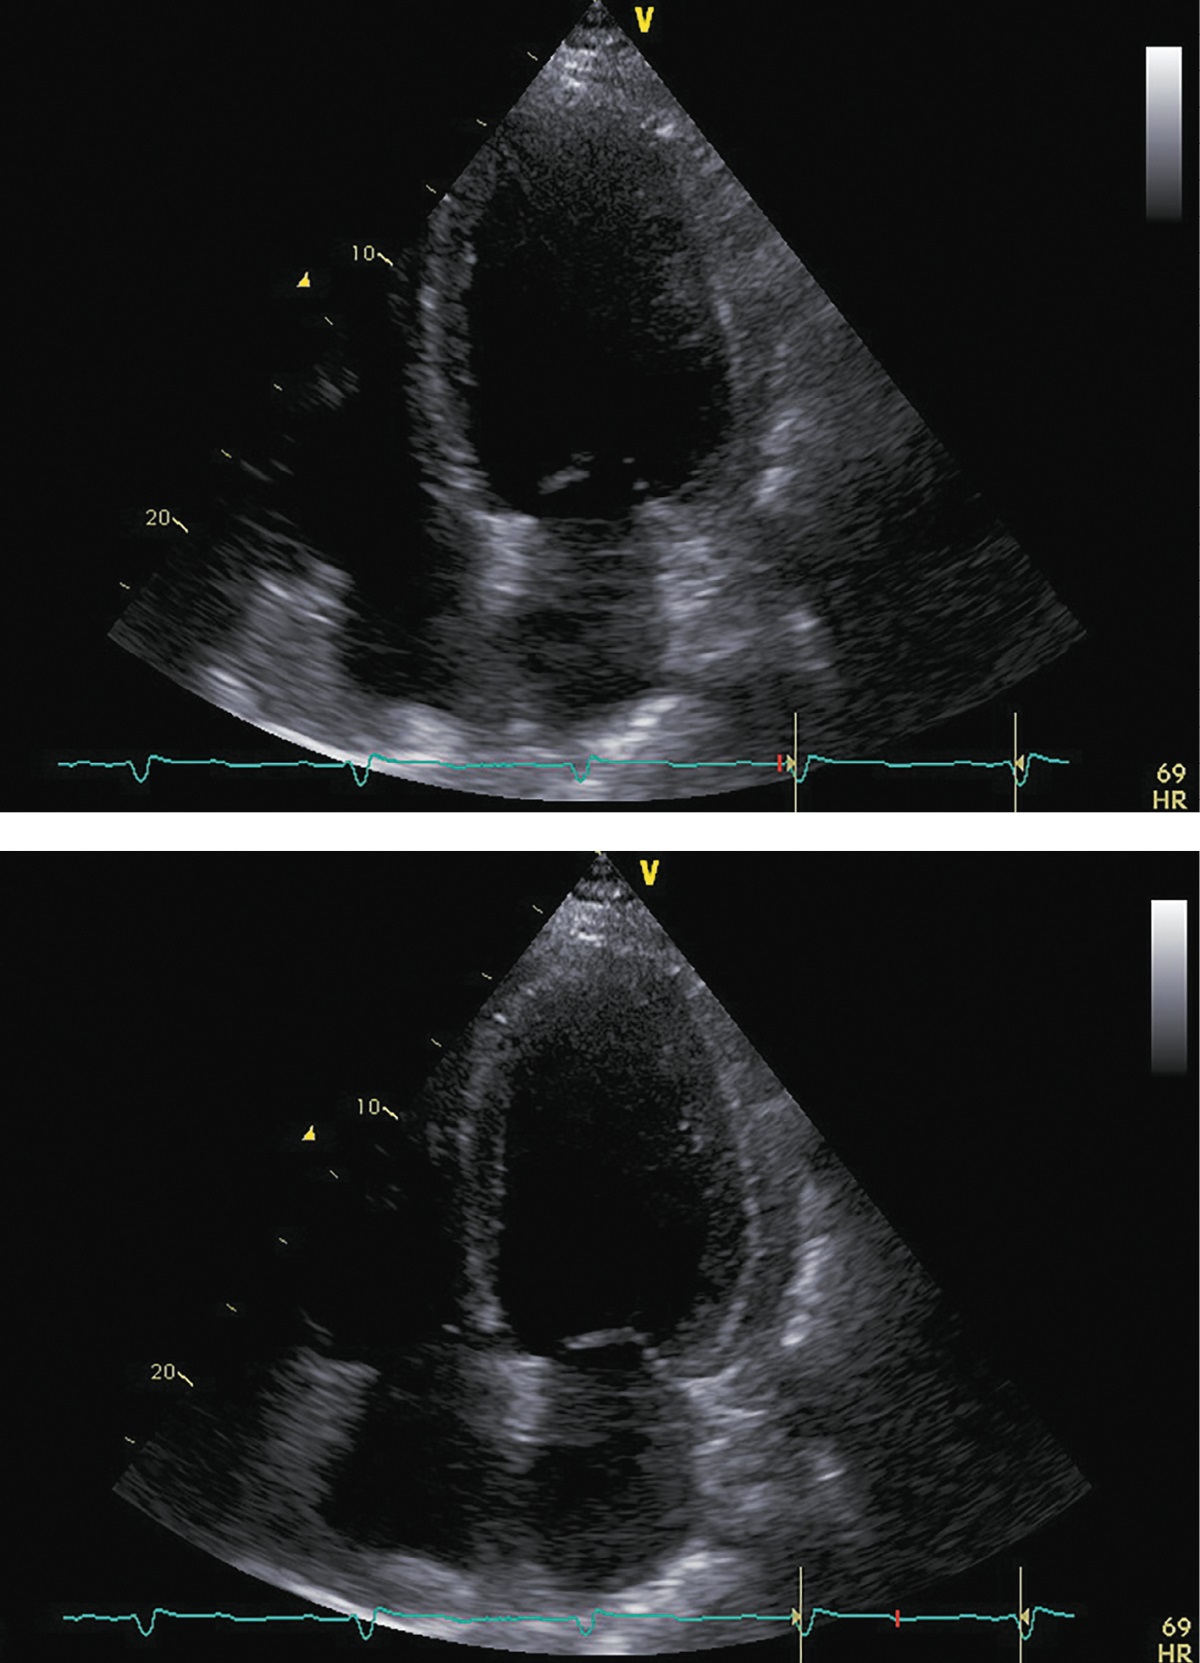

В ноябре 2017 г. пациент госпитализирован повторно для проведения нейрохирургического лечения. Пациент указал, что принимал предписанную терапию в полном объеме. Каких-либо нежелательных лекарственных реакций не выявлено. На фоне лечения симптомы ХСН заметно регрессировали, толерантность к физическим нагрузкам возросла до уровня II ф.к. по NYHA. Физикальной симптоматики легочного застоя и увеличения печени не отмечалось. При контрольной ЭХОКГ (рис. 5; табл. 3) выявлены уменьшение размеров и объемов левого желудочка, значительное увеличение ФВ ЛЖ (до 43%) и снижение класса диастолической дисфункции ЛЖ.

Рисунок 5. ЭХОКГ перед аденомэктомией.

Примечание: верхушечная 4-камерная позиция (сверху представлен кадр в диастолу, снизу — в систолу).

Таблица 3. ЭХОКГ-показатели перед аденомэктомией

|

Показатель |

Значение/индекс |

Объем левого предсердия |

100 мл/54 мл/м² |

Передне-задний размер левого желудочка |

7,20 см/2,89 см/м² |

Конечно-диастолический объем левого желудочка |

285 мл/117 мл/м² |

Конечно-систолический объем левого желудочка |

162 мл/67 мл/м² |

Локальная кинетика левого желудочка |

умеренный диффузный гипокинез |

Фракция выброса левого желудочка (усреднение по 4- и 2-камерным верхушечным позициям) |

43% |

Диастолическая функция левого желудочка |

градация II, псевдо-нормальный тип |

Конечно-диастолическая площадь правого желудочка |

25,0 см²/10,0 см²/м² |

Конечно-систолическая площадь правого желудочка |

12,0 см²/4,8 см/м² |

Фракция систолического уменьшения площади |

52% |

Расчетное систолическое давление в легочной артерии |

43 мм рт.ст. |